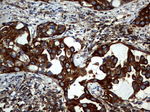

KRT7 Monoclonal Antibody (OTI3B7), TrueMAB™

Cytokeratin 7 blocks interferon-dependent interphase and stimulates DNA synthesis in cells. Involved in the translational regulation of the human papillomavirus type 16 E7 mRNA (HPV16 E7).

蛋白别名: CK-7; cytokeratin 7; Cytokeratin-7; K7; keratin 7, type II; keratin, 55K type II cytoskeletal; keratin, simple epithelial type I, K7; Keratin, type II cytoskeletal 7; Keratin-7; Sarcolectin; type II mesothelial keratin K7; Type-II keratin Kb7